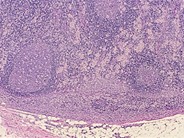

Toxoplasmosis - 5.

Category: Reactive Marrow > Reactive changes